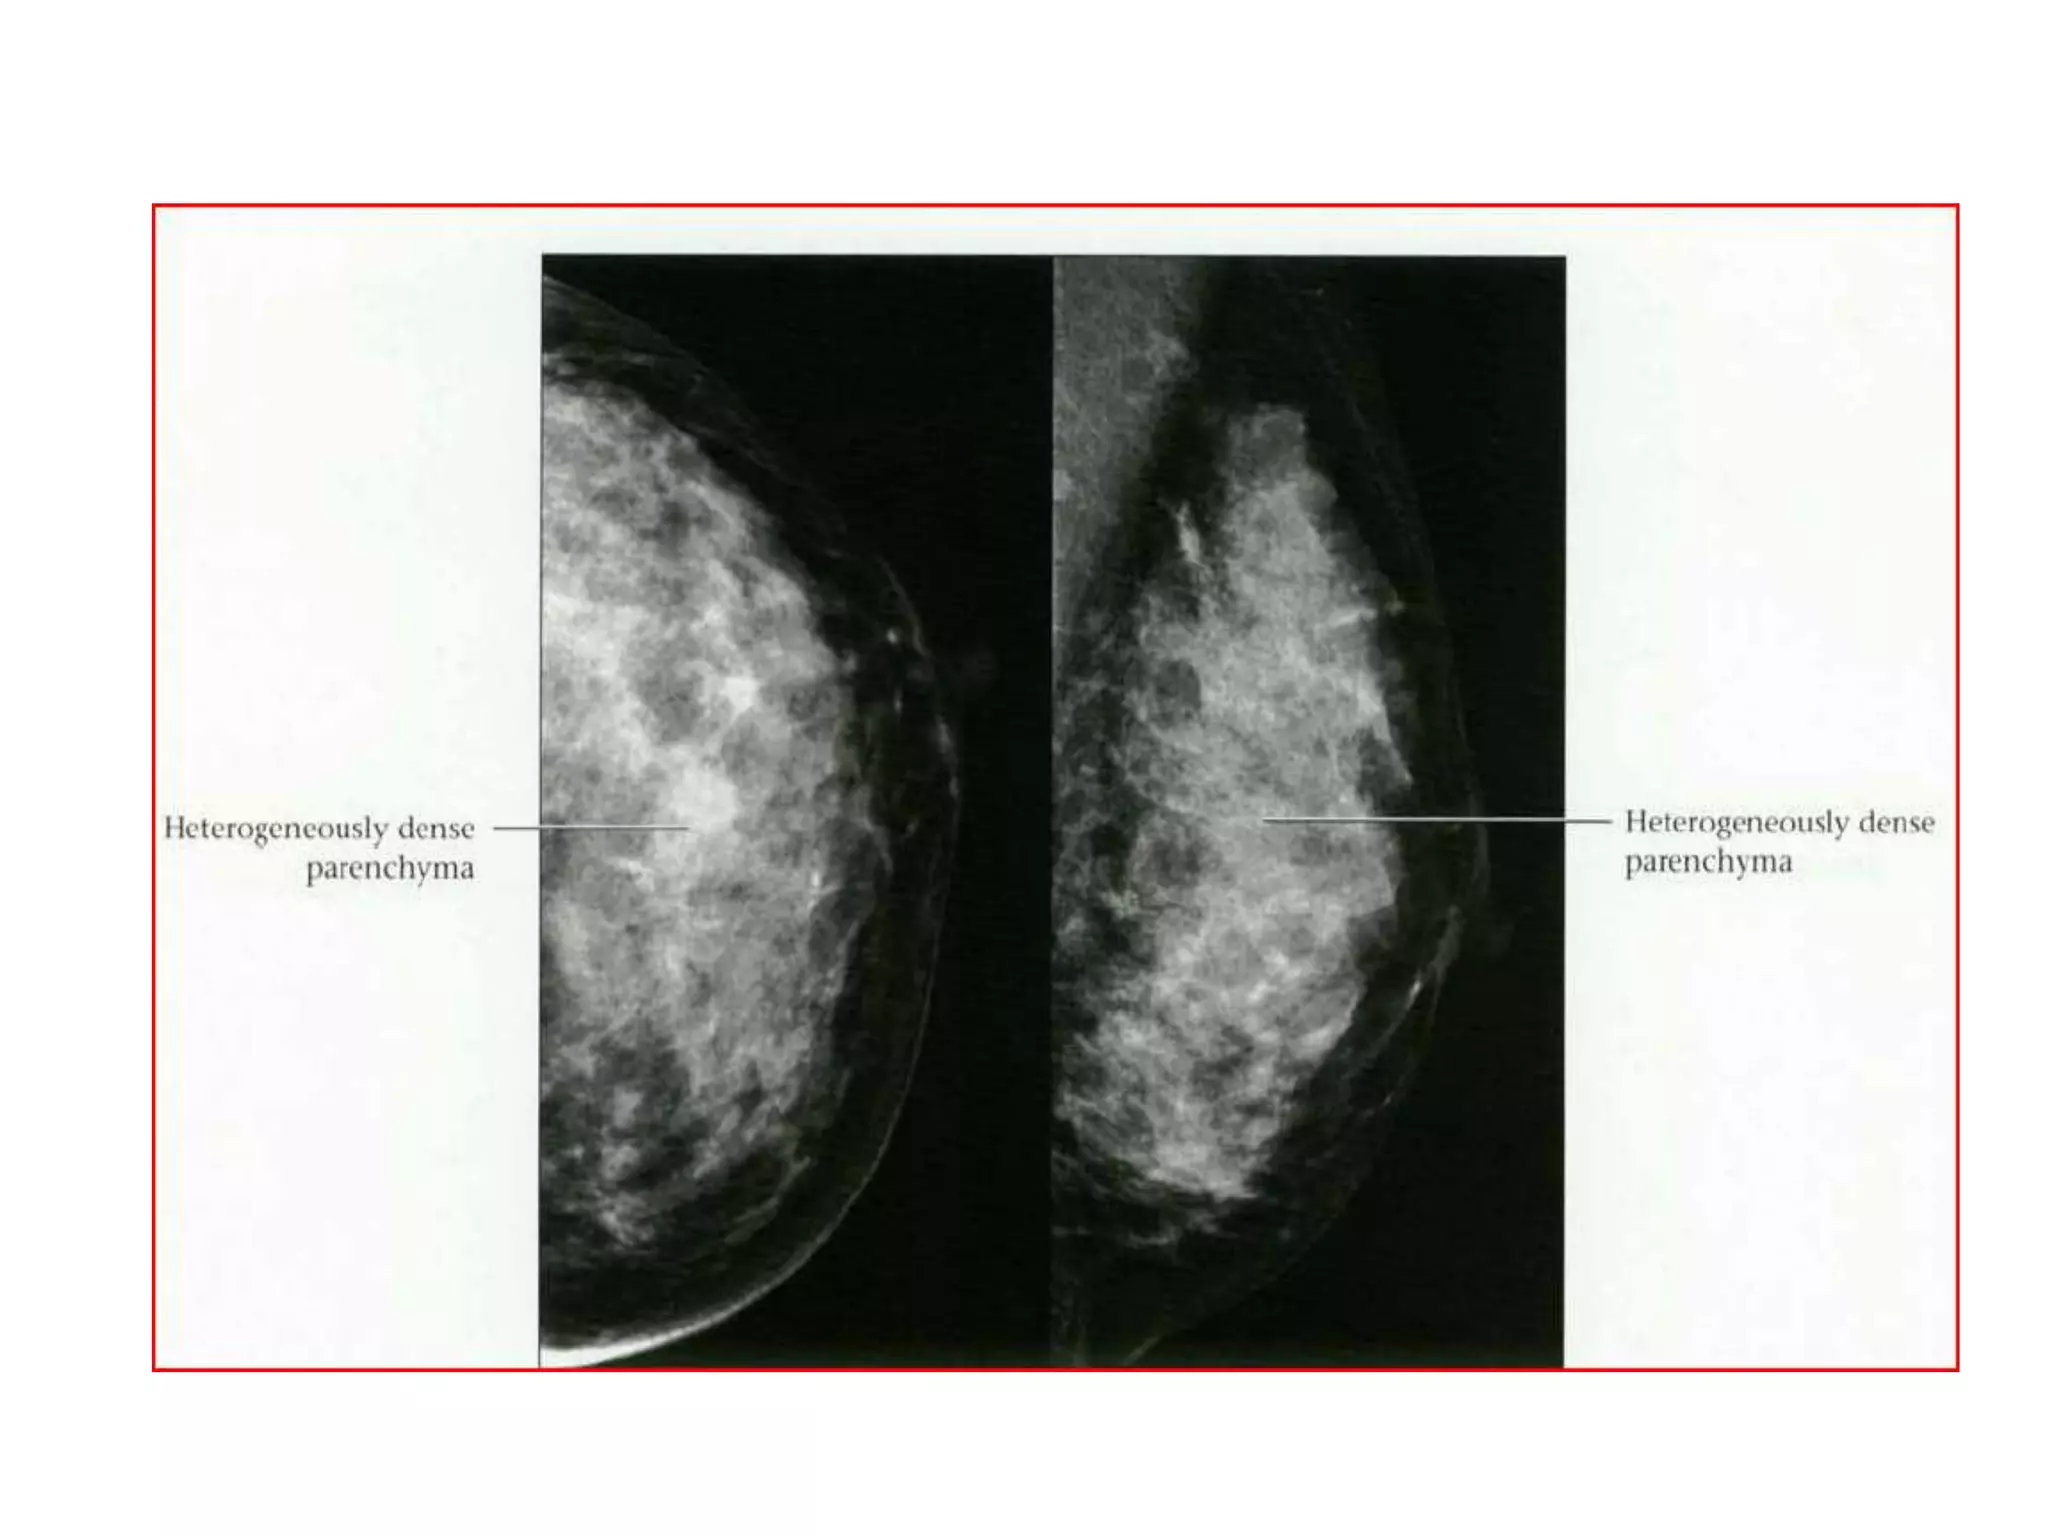

BI-RADS BREAST COMPOSITION

• The American College of Radiology Breast

Imaging and Reporting Database System (BIRADS)divides breast composition into four

categories:

• 1) almost entirely fat,

• 2) scattered fibroglandular densities

(approximately 25-50% glandular),

• 3) heterogeneously dense (51-75% glandular),

• 4) extremely dense (greater than 75% glandular).